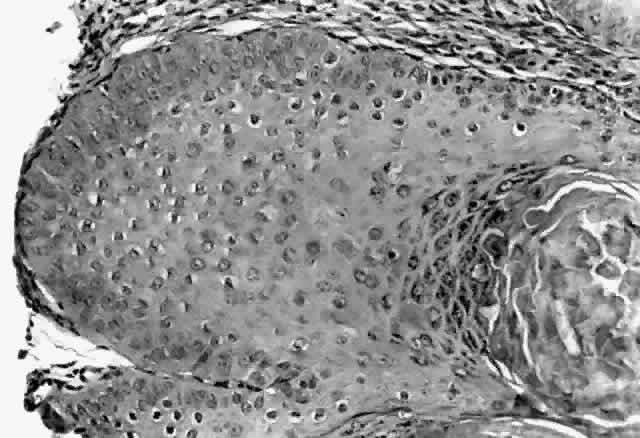

Molluscum contagiosum is a papule with lobular downgrowth of epithelium into the dermis and a central “crater” on the surface (Fig. 11). The epithelium and infected cells demonstrate hyperplasia. Basal cells divide more rapidly (6.1 day turnover decreasing to 3.4 days) and infected cells show more rapid migration through the epithelium as well as cessation of host DNA transcription.121,122 Each lobule demonstrates a progression from base to top. The malpighian cells contain eosinophilic elementary bodies (Fig. 12). These coalesce to form a hyaline molluscum body (HendersonPaterson body).123 The cytoplasmic molluscum bodies increase in size until they distort and displace the nucleus, sometimes becoming larger than the original host cell (Fig. 13). At the top of the lobule in the granular cell layer, the Henderson-Paterson inclusion body changes from eosinophilic to basophilic. When the overlying stratum corneum loses its integrity, the crater is formed (see Fig. 10). Microdissection revealed124 and scanning electron microscopy confirmed125 the presence of a sac surrounding the viral inclusion body within each cell, which has been speculated to provide an immunologically sheltered site for viral reproduction.

Fig. 11. Molluscum contagiosum, histology. Low-power view of lobular epithelial downgrowth and central umbilicated crater. (Original magnification × 50)

Fig. 12. Molluscum contagiosum, histology. Evolution of molluscum bodies from base (left) to center of lobule (right). (Original magnification × 200)

Fig. 13. Molluscum contagiosum, histology. High-power view of transition zone. Molluscum bodies are apparent (right). Note the dark, displaced nuclei. (Original magnification × 400)